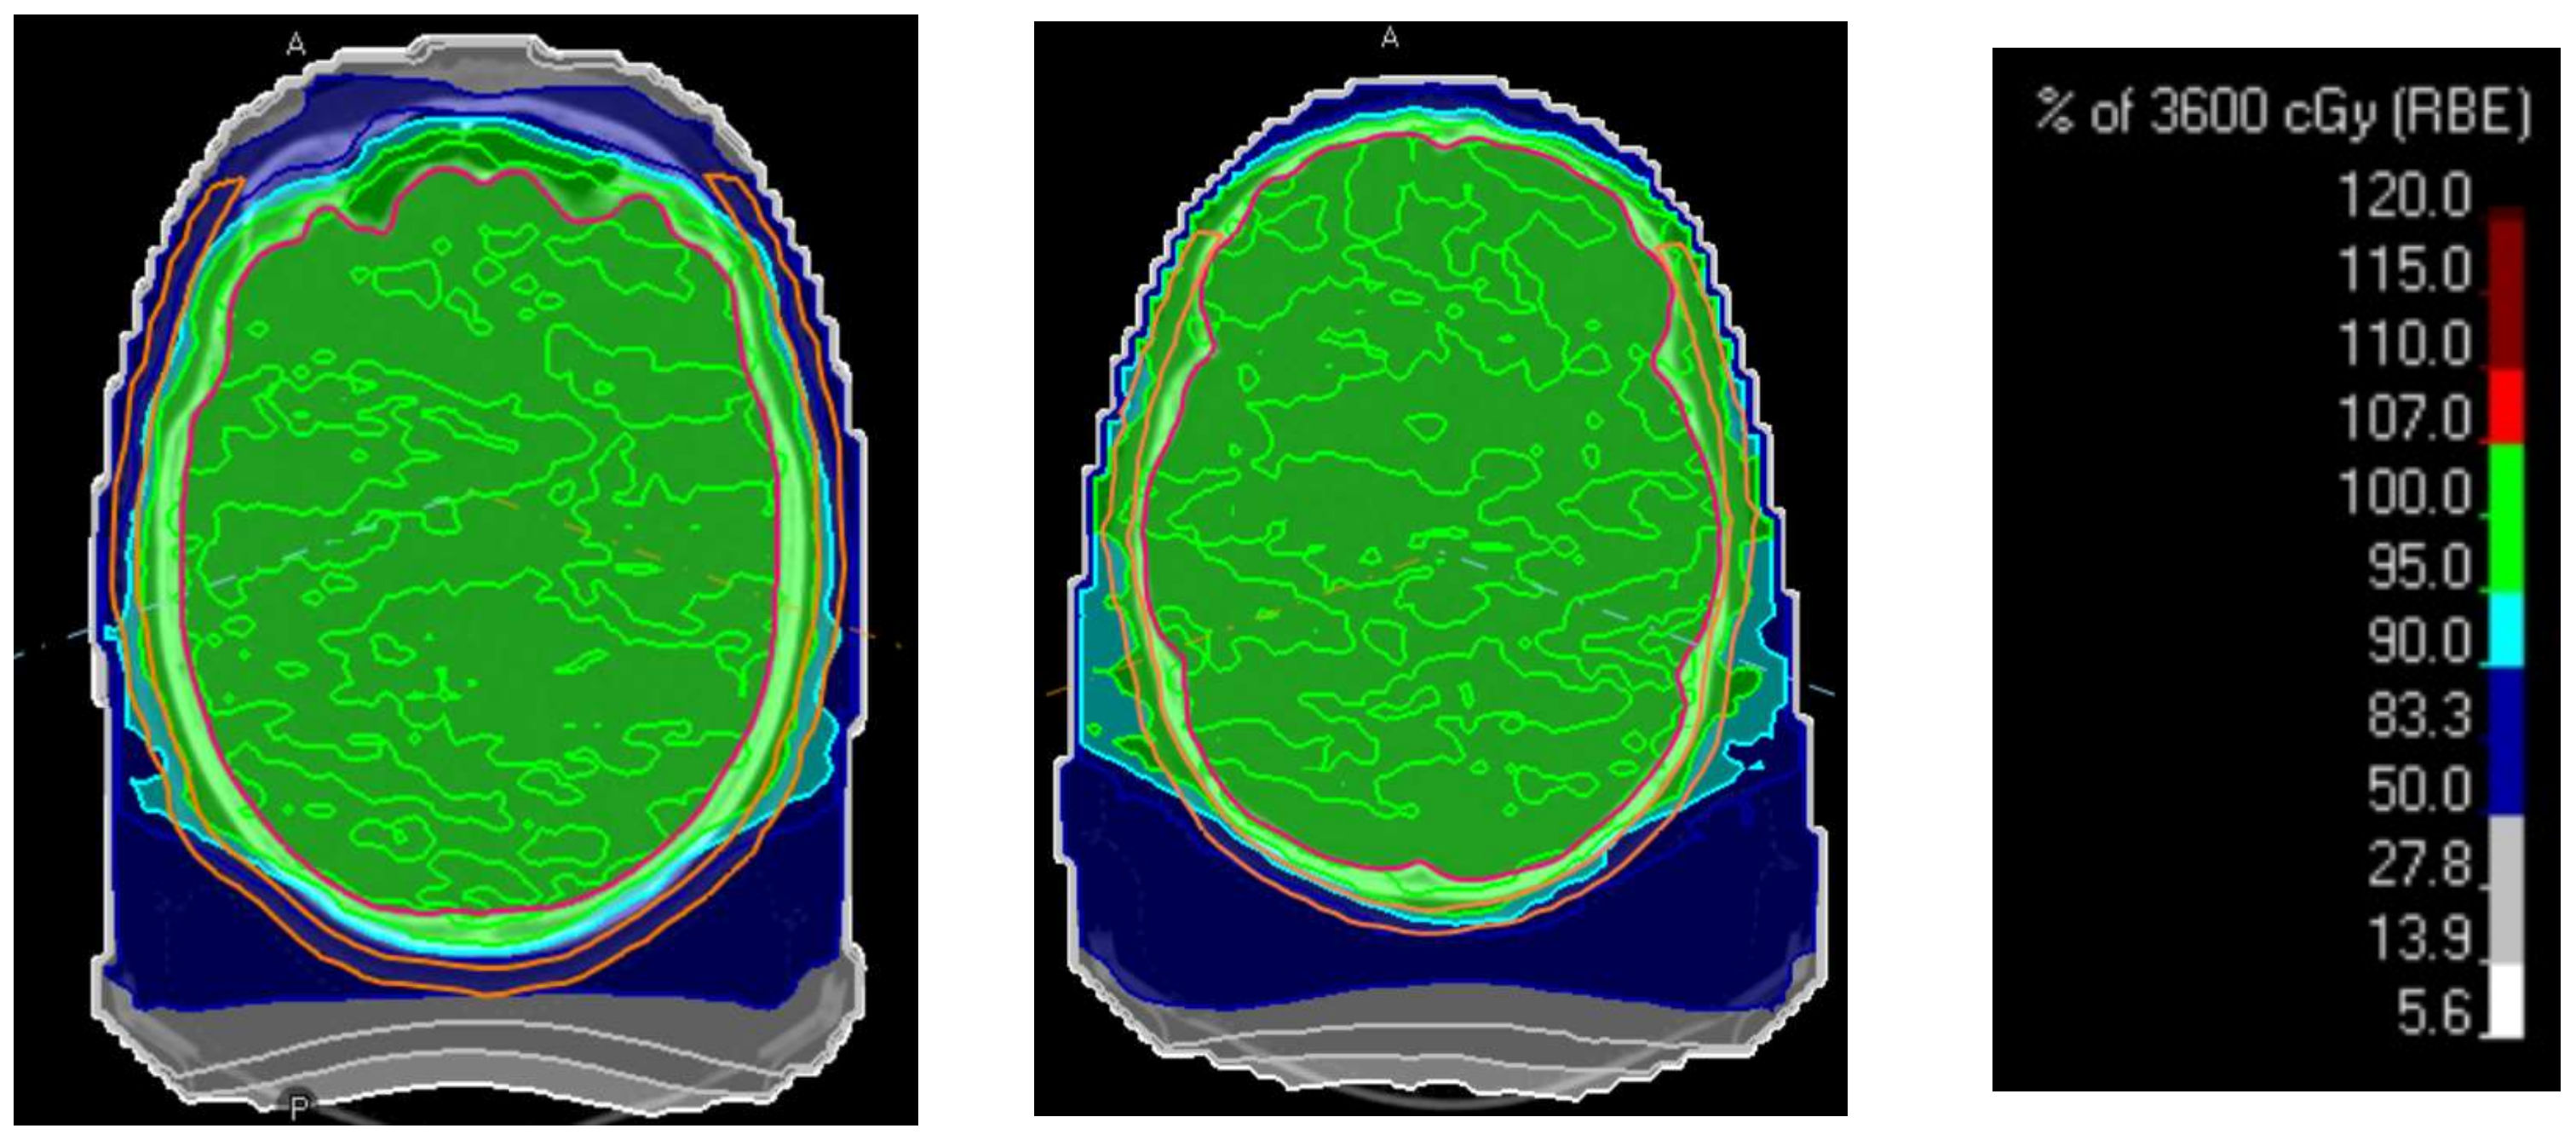

Based on Figure 9, it is apparent that V30 Gy is much lower for cases 1 and 2 (adults) than for the remaining cases (pediatric patients). Although less pronounced, this difference is also present for V21 Gy (see Figure A11: V21 Gy to Scalp5). The reason for this difference is the presence of the larger separation between the CTV-brain and skin surface, which in adults, is provided by thicker cranial bones and subcutaneous tissue, sufficient for the distal fall-off dose gradient, while for pediatric patients, the separation is too small to allow sparing while providing adequate CTV coverage (Figure 10).

Figure 10.

Illustration of the separation between the CTV-brain (red) and scalp (orange): adult case (left) and pediatric case (right).

The reduction shown in the figures as well as the dose volume histograms can be also illustrated by superimposing the isodoses onto the skin surface contour (Figure 11). The differences in the level of scalp sparing between the adult and pediatric cases are apparent. Furthermore, the effect of the superficial spot removal is visible in both cases. Finally, the redistribution of the high dose area toward the posterior section is visible when the third (posterior) field is added.

The shape of the high dose region in the adult case (notice the 80% IDL in Figure 11, two-field beam arrangements) follows the shape of the entrance dose, while for the pediatric case (see the 90% IDL), it is more consistent with the exit dose. This observation illustrates the contributions of entrance and exit doses to the total scalp dose. The addition of the third field direction also redistributes the high dose region more uniformly to the dorsal part of the scalp.